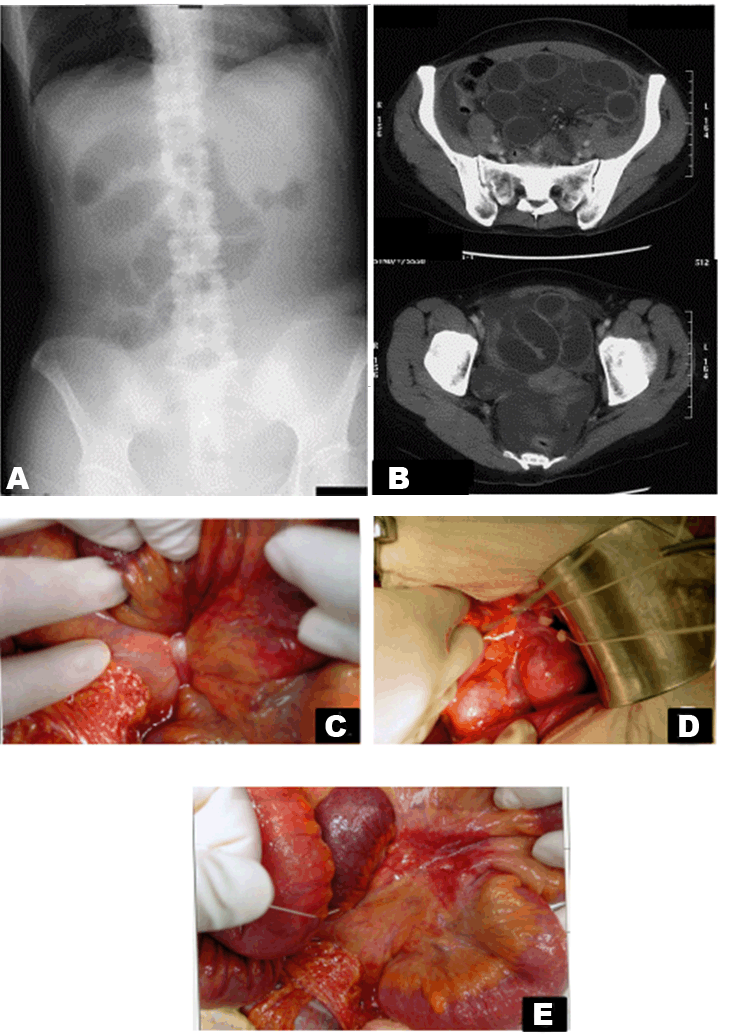

Four days later, her stomachache had worsened, so we did another X-ray and CT scan (Figure 2).

Laboratory results had not changed (only leukocytosis was found) and there was no indication of intestinal disorders. We found an increase in the size of the small bowel loops with air on the X-ray. The CT scan showed distended loops and fluid in the Douglas' pouch. There was large volume ascites in the abdomen, so we decided to operate for the ileus.

For her safety, we selected a laparotomy. At surgery, we saw the ascites (serous) about 700 ml. The small intestines were edematous, the mesentery was strangulated by the fallopian tube and the blood flow to the intestine was decreased.

We resected the fallopian tube and proper ligament of the ovary and released the hernia. We washed the intraperitoneal with warm saline solution. We did not need to resect the intestine because of the recovery of the blood flow (Figure 2C-E).

Figure 2: (A, B) The X-ray and computed tomography (CT) scan were taken four days later. X-ray showing an increase in the small intestinal gas. Computed tomography scan showing the distended loops with air-fluid level in the Douglas' pouch. Mesenteries and blood vessels concentrate in the vicinity of uterus. The distended loops push the uterus to contralateral and ventral side. In addition, the loops push the sigmoid colon and rectum to the back side, (C) The mesentery was tightened by the Fallopian tube, (D) The situation after dissection of the fallopian tube and ligament of ovary, (E) The mesentery congested with blood.